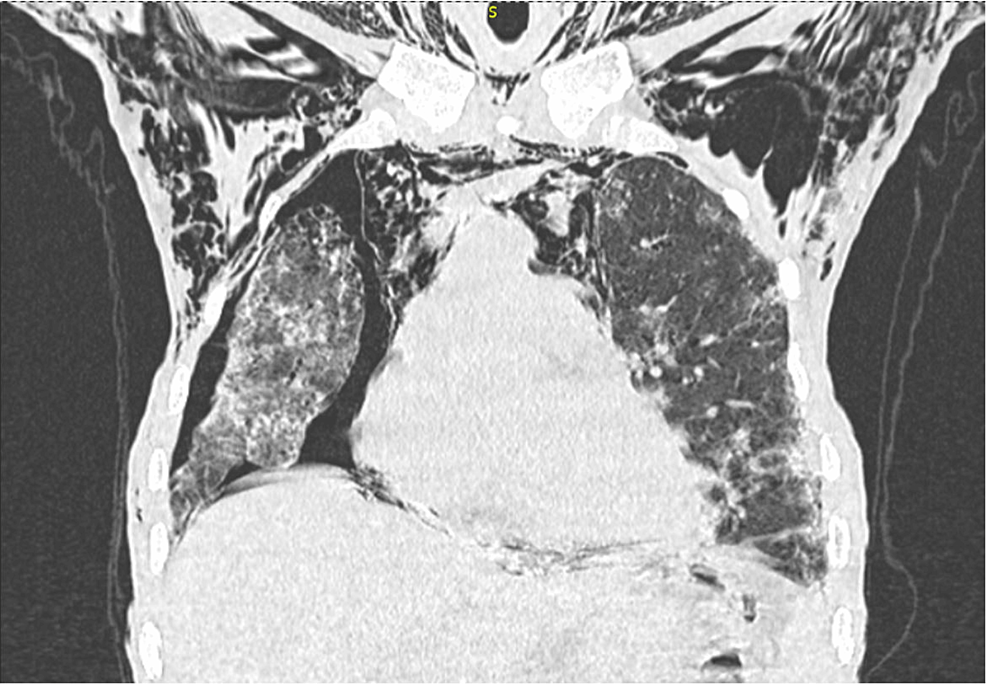

Chest CT showing the bilateral lung interstitial infiltrations Mgus Interstitial Lung Disease interstitial lung diseases are characterised by inflammation or fibrosis within the interstitial space, the primary consequence. Interstitial lung diseases (ilds) are a group of heterogeneous diseases characterized by inflammation. multiple myeloma presenting as interstitial lung disease. interstitial lung diseases (ilds) refer to a heterogeneous and complex group of conditions characterized by. Ada tin wei ma, regina cheuk. Mgus Interstitial Lung Disease.